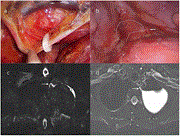

A cyst in the mist: bronchogenic mediastinal cysts

Sowmya Prasanna Kumar Menon and others

Journal of Surgical Case Reports, Volume 2023, Issue 1, January 2023, rjad020, https://doi.org/10.1093/jscr/rjad020